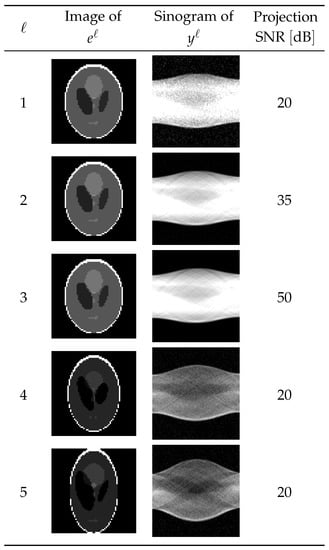

To evaluate the performance of the learned optimizer , we validated it on a test dataset consisting of data not included in the training and validation datasets. The properties described below are common to all of the test datasets. We will discuss the results for five of the test data pairs shown in Figure 9. The first test data item () was a pair of a projection with an SNR of 20 dB and the expected reconstructed image . In the second and third test data pairs ( and 3), the expected reconstructed images and equaled but with different Sn Rs of the projection. On the other hand, in the fourth and fifth test data pairs ( and 5), the expected reconstructed images and were different from and from each other, but the noise levels of the projections were 20 dB.

Figure 9.

Dataset for testing.